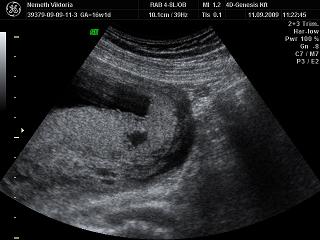

Nagyon boldog névnapot a pici fiúnak!